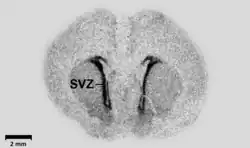

Uma autorradiografia, em certas literaturas também citada como auto-radiografia, é uma imagem em um filme de raios X ou emulsão nuclear produzido pelo padrão de emissões de decaimento (e.g., partículas beta ou raios gama) de uma distribuição de uma substância radioativa. Alternativamente, a autoradiografia também é disponível como imagem digital (autorradiografia digital), devido ao recente desenvolvimento de detectores de gás por cintilação[1] ou sistemas de imagem por fosforescência de terras raras.[2] O filme ou emulsão é posicionado na seção de tecido marcado para obter a auto-radiografia (também chamado de autorradiograma). O prefixo auto- indica que a substância radioativa está dentro da amostra, diferentemente do caso da historradiografia ou microrradiografia, nas quais a amostra é marcado usando uma fonte externa. Algumas autorradiografias podem ser examinadas microscopicamente para localização de grãos de prata (como no interior ou exterior de células ou organelas)na qual o processo é denominado micro-autorradiografia. Por exemplo, micro-autorradiografia foi usada para examinar se atrazina estava sendo metabolizado pela planta antócero ou por microorganismos epifíticos na camada de biofilme circundando a planta.[3]